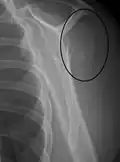

Proximal

Proximal humerus fractures most often occur among elderly people with osteoporosis who fall on an outstretched arm.[9] Less frequently, proximal fractures occur from motor vehicle accidents, gunshots, and violent muscle contractions from an electric shock or seizure.[10][5] Other risk factors for proximal fractures include having a low bone mineral density, having impaired vision and balance, and tobacco smoking.[11] A stress fracture of the proximal and shaft regions can occur after an excessive amount of throwing, such as pitching in baseball.[6]

Definitive diagnosis of humerus fractures is typically made through radiographic imaging. For proximal fractures, X-rays can be taken from a scapular anteroposterior (AP) view, which takes an image of the front of the shoulder region from an angle, a scapular Y view, which takes an image of the back of the shoulder region from an angle, and an axillar lateral view, which has the patient lie on his or her back, lift the bottom half of the arm up to the side, and have an image taken of the axilla region underneath the shoulder.[9] Fractures of the humerus shaft are usually correctly identified with radiographic images taken from the AP and lateral viewpoints.[12] Damage to the radial nerve from a shaft fracture can be identified by an inability to bend the hand backwards or by decreased sensation in the back of the hand.[5] Images of the distal region are often of poor quality due to the patient being unable to extend the elbow because of pain. If a severe distal fracture is suspected, then a computed tomography (CT) scan can provide greater detail of the fracture. Nondisplaced distal fractures may not be directly visible; they may only be visible due to fat being displaced because of internal bleeding in the elbow.[7]